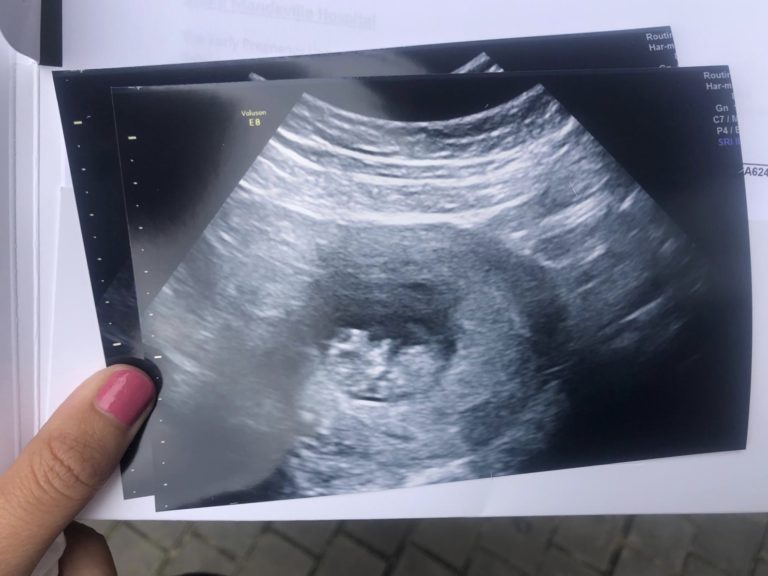

S: The first time we would properly see Em and hopefully our little bean was at our 10 week scan booked in for all 4 of us to go to in Watford. I felt so excited during the 4/5 days leading up to the scan. We had literally never seen one of those screens with anything positive on it so I was hoping this might be the first time that we would. But also knew I’d need to be mindful that we still weren’t classed as being in any sort of safe zone (Is there really a safe zone in pregnancy anyway).

S: The day of the 10 week scan the 4 of us were also headed down to a friends wedding in the Cotswolds so we went to the clinic before the journey down. I woke up with butterflies. I was actually far more excited than nervous. I kept asking Jack how he felt and he said ‘I’m just not thinking about it’, which has always been his way of dealing with it.

S: We sat in the waiting room and the nerves kicked in. Em was so calm though. We all went into the room and I held Em’s hand and then a few minutes later our baby could be seen on the big projector screen. It looked more like a baby than the previous scans with a clear head and small bud like arms and the heartbeat I had been longing to see for years was right there beating away. It was totally surreal.

E: I haven’t had any sickness in any of my pregnancies, so it always surprises me to see an actual baby wriggling around in my tummy- even third time around knowing that this is what happens! It was really nice having James in the room too- it was like we had the full team behind this little being all there watching this complete miracle chilling out, being all carefree and cute! The boys kept making jokes but had to stop as I kept laughing and moving the baby! It was just so lovely, and so surreal too

S: To see that little bean wriggling around was the most incredible thing I’d ever seen. Although I still felt a little detached mainly because I think I’m still in shock from it being our baby in there, I definitely still felt hugely emotional. I actually think Jack went into a trance not quite believing that what we were looking at on the screen was actually a baby.

We came out and told our friends and family who knew about the scan that all was still ok and I do believe this may have been the first time we both thought ‘Wow what If we do actually have a baby in 7 months’.